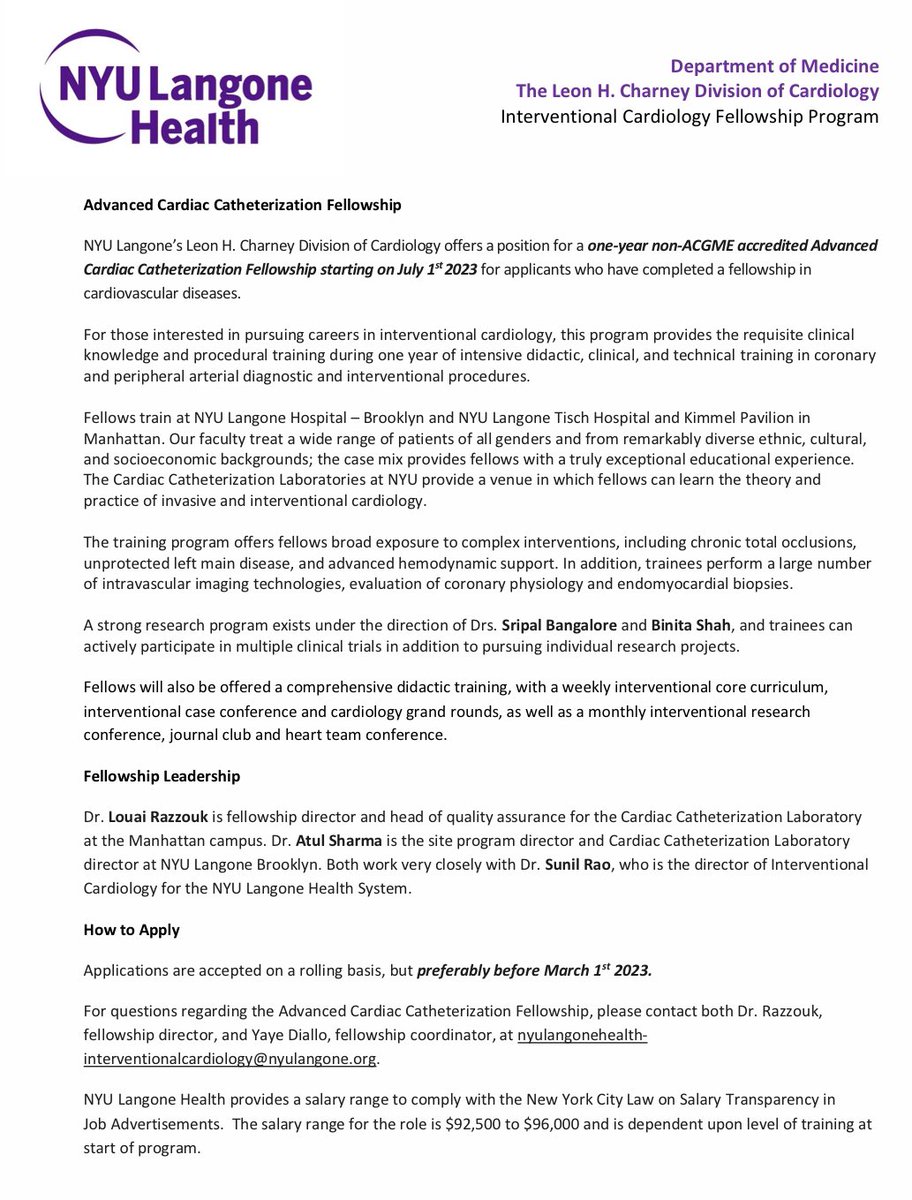

1-year non-ACGME Interventional Cardiology Fellowship NYU Langone Health starting 7/1/2023- at both BK & Manhattan campuses, great coronary & peripheral training. Outstanding and dedicated faculty at both campuses. Application deadline 3/1. Details below.